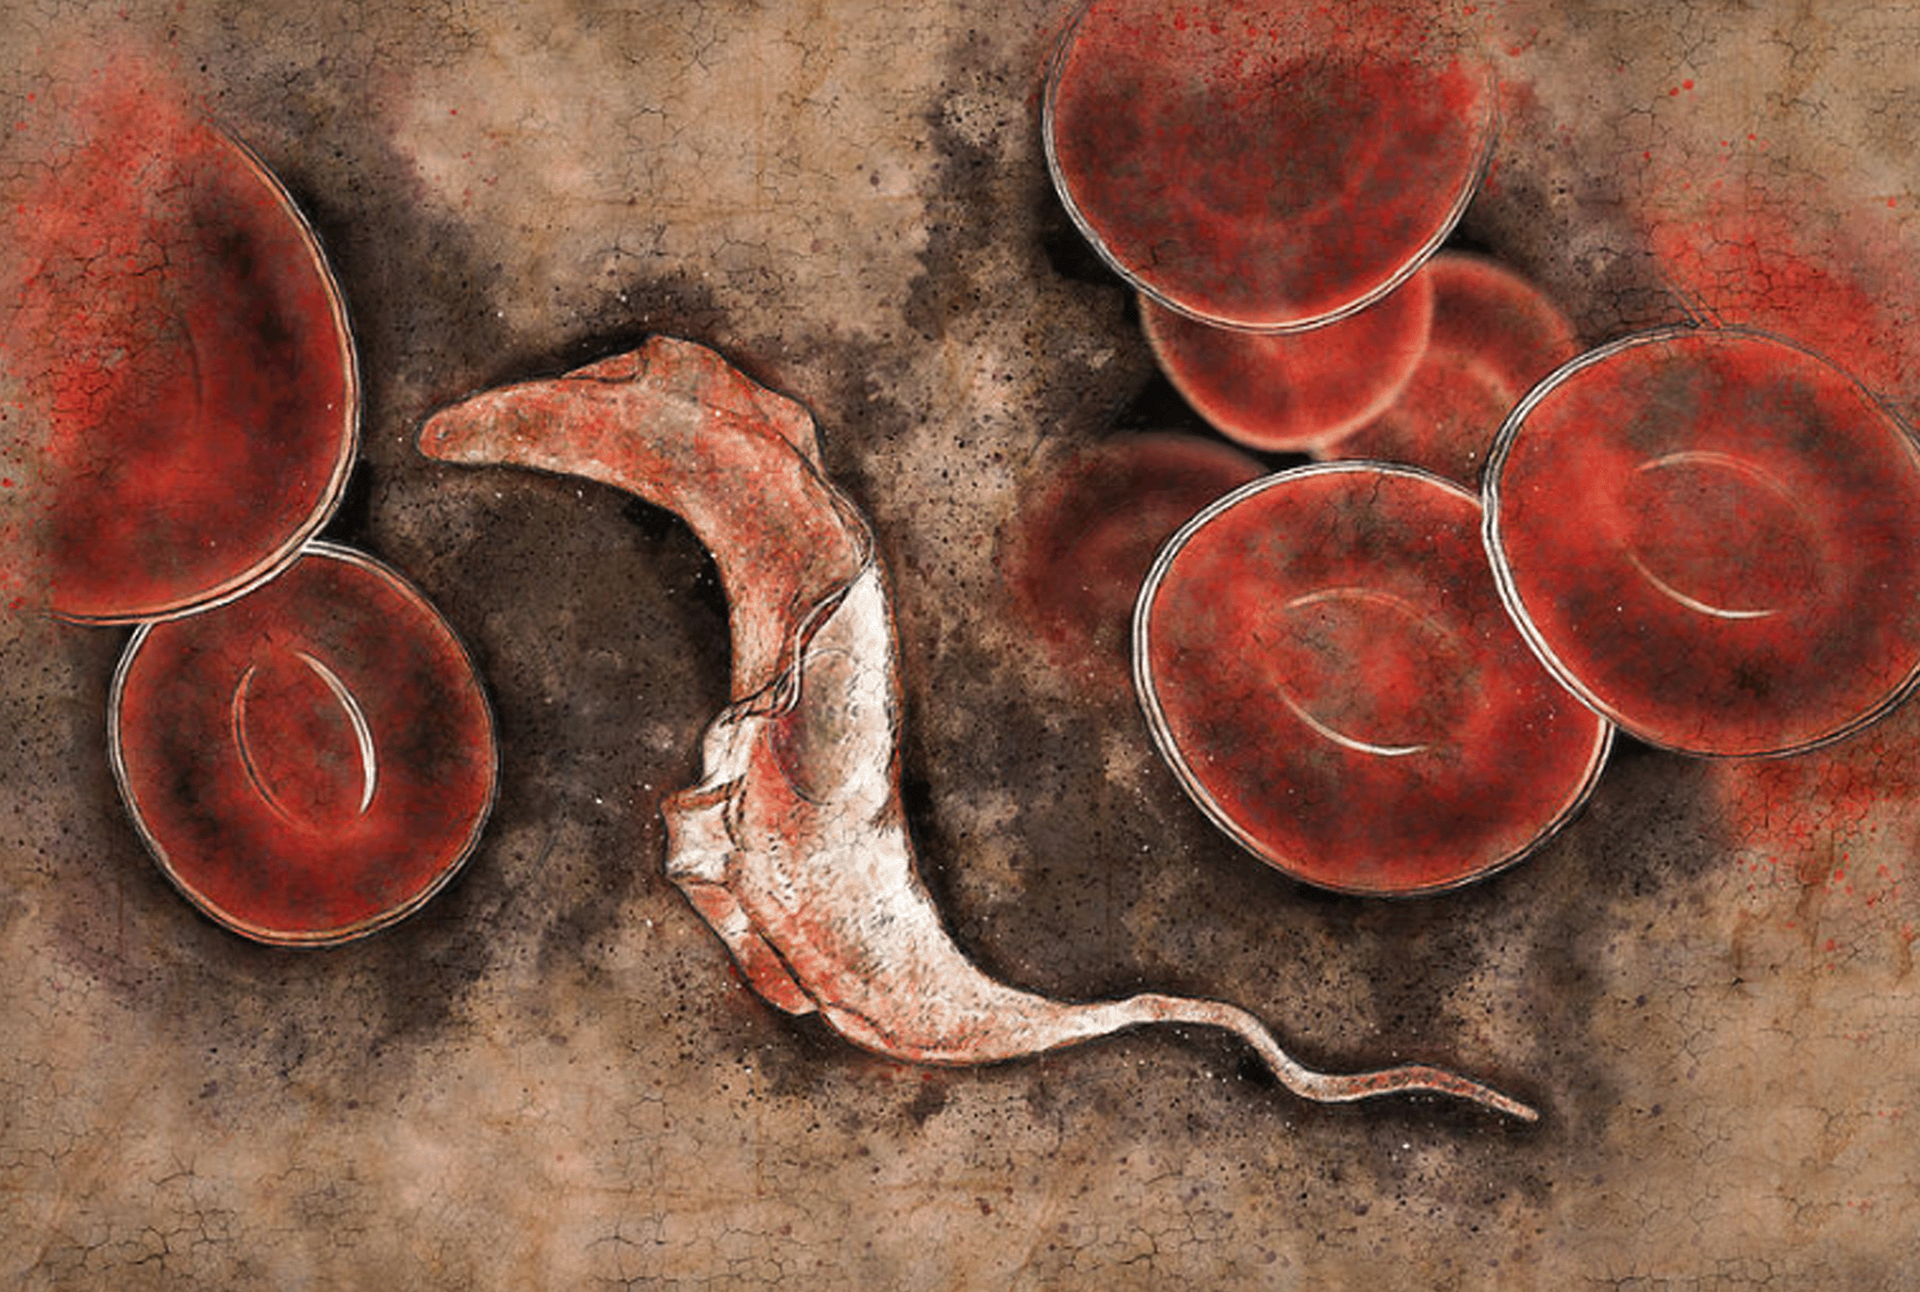

التصدي لداء شاغاس:

الكشف المبكر وصون الحياة

هناك ما بين 6 و7 ملايين شخص مصاب بالداء في العالم

هناك ما يقرب من 000 12 حالة وفاة مرتبطة بالداء كل عام

تُسجَّل 000 30 إلى 000 40 حالة إصابة جديدة كل عام

نسلّط الضوء، في عام 2024، على داء شاغاس والمعاناة التي يسبّبها للناس وندعو إلى إتاحة الرعاية والخدمات الصحية بشكل منصف لجميع المصابين بالداء.

ويتمثل موضوع عام 2024 في التصدي لداء شاغاس: الكشف المبكر وصون الحياة، ويهدف إلى إذكاء وعي الجمهور بداء شاغاس وتوفير المزيد من التمويل والدعم للتشخيص المبكر والمبادرات الشاملة في مجال رعاية المتابعة.

وينتشر داء شاغاس بين الفئات السكانية الفقيرة في أمريكا اللاتينية القارية، غير أنه يتم الكشف عنه بشكل متزايد في بلدان وقارات أخرى.

وغالباً ما يُطلق عليه "المرض الصامت والمكتوم الصوت" لأن معظم المصابين بعدواه لا تظهر عليهم أي أعراض أو تظهر عليهم أعراض خفيفة للغاية. وهناك ما يقرب من 6 إلى 7 ملايين شخص مصاب بعدوى داء شاغاس في العالم، و000 10 حالة وفاة كل عام.